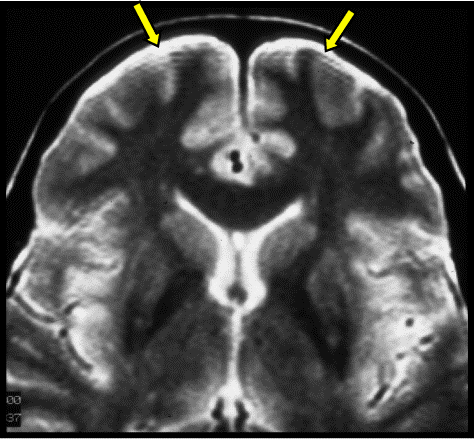

How can Gibbs artifact be minimized

Truncation errors (Gibbs artifact) can be minimized by increasing the number of phase-encode steps or by reducing the field of view.

What was the most likely step taken to eliminate the artifact seen in the first image?

Increasing the matrix size decreased truncation artifact (aka Gibbs, or ringing).

choosing a smaller FOV can also help eliminate this artifact